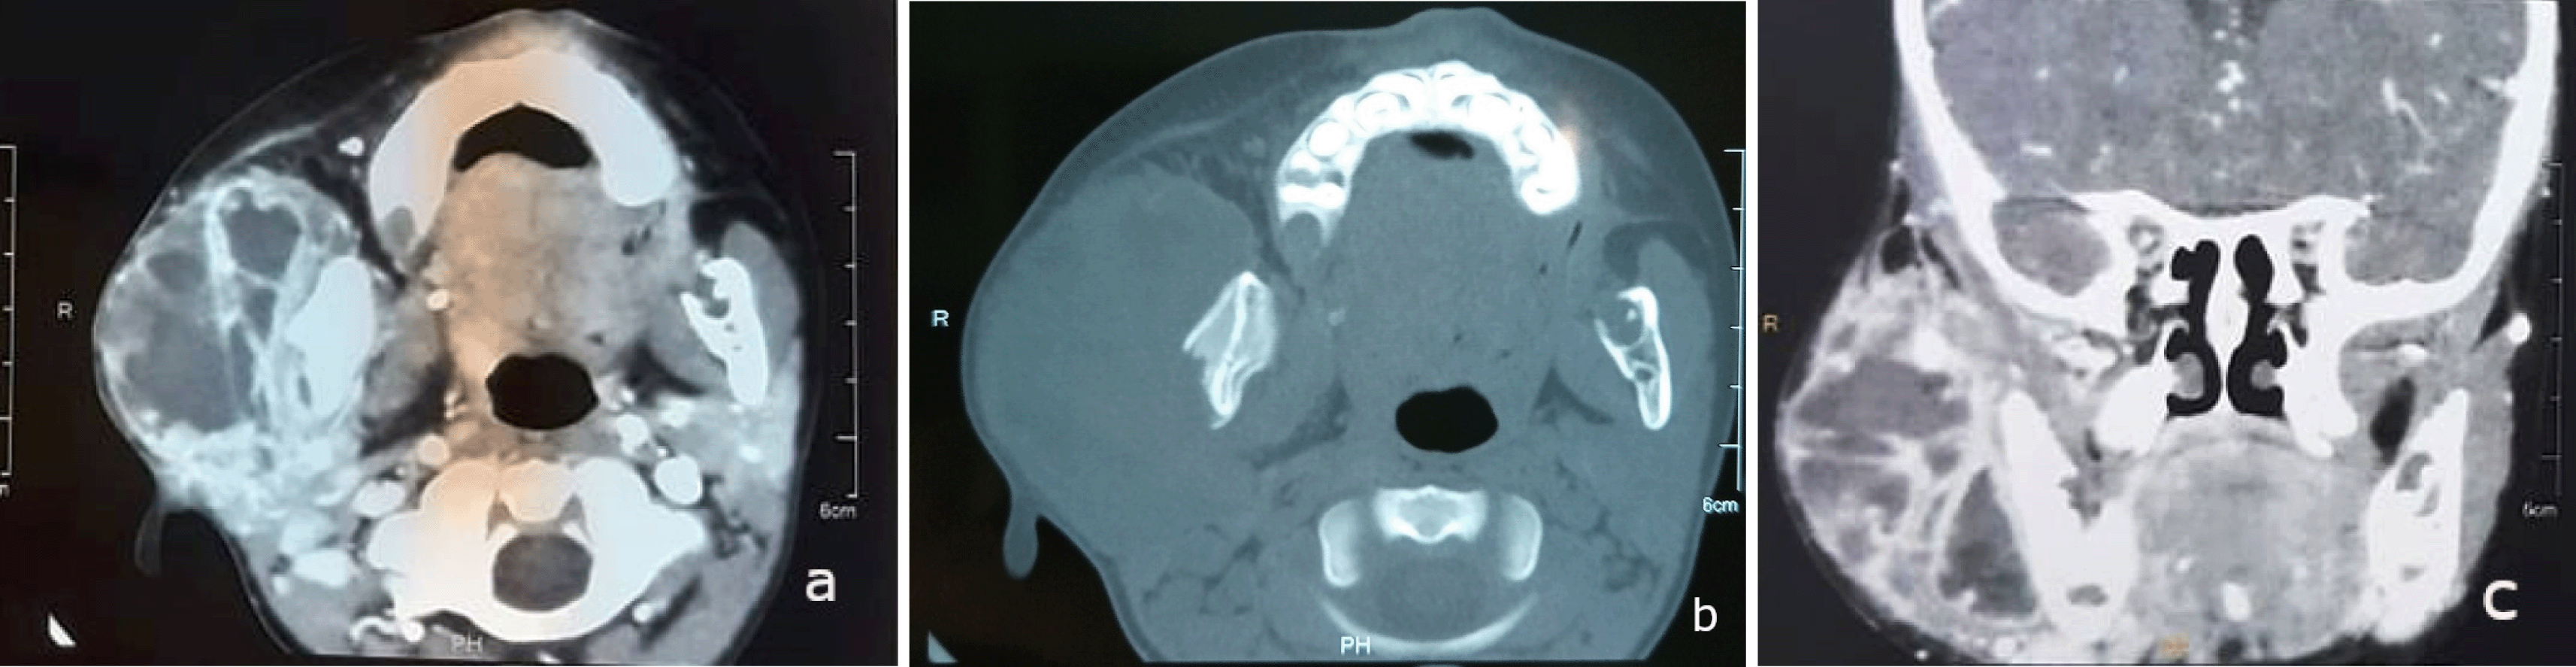

Initial laboratory tests indicated systemic inflammation. Within 24 hours, a contrast-enhanced CT scan revealed a solid cystic mass in the right parotid gland, measuring 44 x 66 mm, poorly defined with heterogeneous contrast. Partial lysis of the right mandibular condyle was observed, without extension to the deep cervico-facial spaces ( Figure 2: a,b,c).

The induration of the swelling, the facial paralysis and the bone lysis observed on CT scan were raising concern for malignancy.